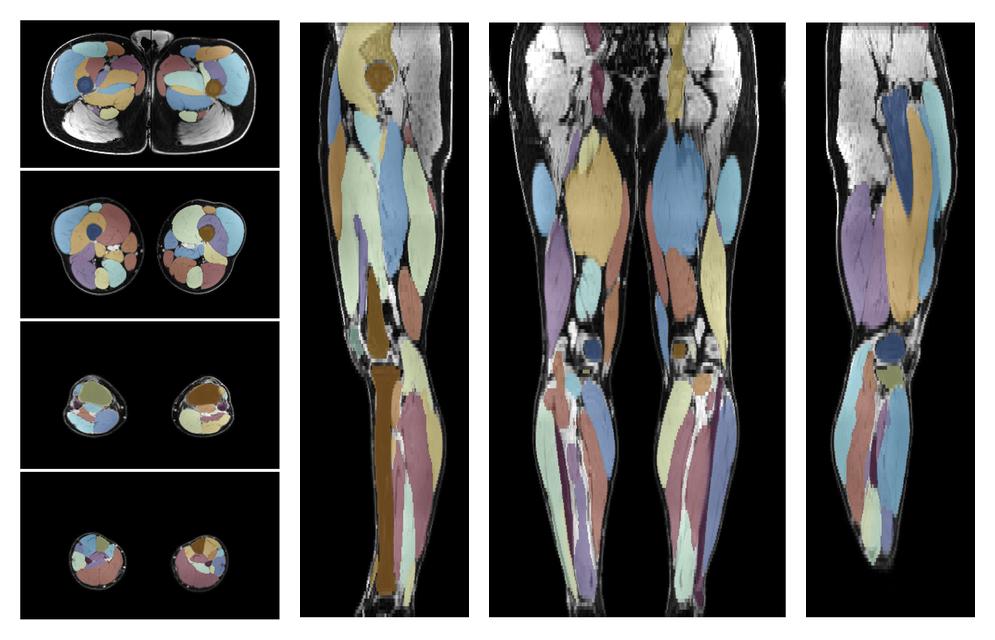

• Automated muscle and bone segmentation.

Overlay of automated muscle segmentation labels on dixon water image.